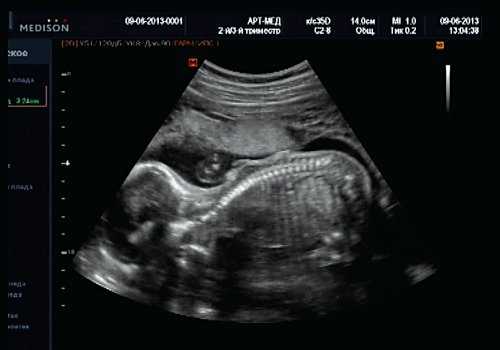

Тем не менее "базовое" УЗИ обычно дополняют исследованием в цветовом энергетическом допплеровском режиме с тщательным анализом для выявления атриовентрикулярного кровотока в четырех камерах сердца (рис. 6a) и в срезе через три сосуда и трахею (рис. 6b). Получив эти срезы, обычно можно успокоить родителей, исключив наличие тяжелых пороков сердца, таких как единственный желудочек, гипоплазия желудочков, полный дефект предсердно-желудочковой перегородки (atrioventricular septal defect - AVSD), атрезия аорты или легочной артерии, а также ряд аномалий расположения артерий.

Рис. 6. Эхокардиография плода на ранних сроках в цветовом энергетическом допплеровском режиме - визуализируются четыре камеры (a) и срез через три сосуда и трахею (b).